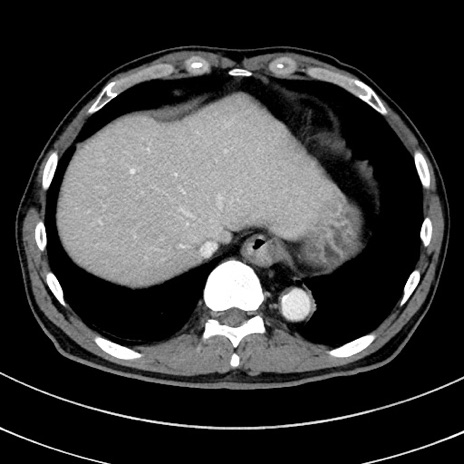

症例8(横断像)

【症例】 60歳代男性

【主訴】 黒色吐物

【現病歴】 4日前から嘔気自覚、2日前の朝食後にも嘔気あり、自分で手で嘔吐反射起こし嘔吐したところ血が混ざっていたため受診。

【既往歴】 5年前汎発性腹膜炎を伴う急性虫垂炎で手術、高血圧、前立腺肥大症、高脂血症

【身体所見】 腹部正中に手術癩痕あり 腹部平坦・軟圧痛なし膨満感あり

【データ】WBC 8400、CRP 4.54